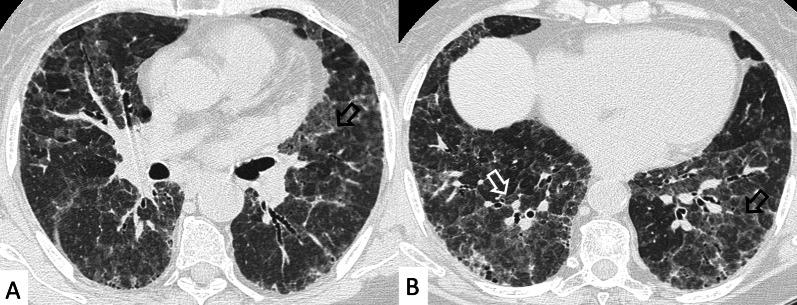

Connective tissue diseases (CTDs) include a spectrum of disorders that affect the connective tissue of the human body; they include autoimmune disorders characterized by immune-mediated chronic inflammation and the development of fibrosis. Lung involvement can be misdiagnosed, since pulmonary alterations preceded osteo-articular manifestations only in 20% of cases and they have no clear clinical findings in the early phases. All pulmonary structures may be interested: pulmonary interstitium, airways, pleura and respiratory muscles. Among these autoimmune disorders, rheumatoid arthritis (RA) is characterized by usual interstitial pneumonia (UIP), pulmonary nodules and airway disease with air-trapping, whereas non-specific interstitial pneumonia (NSIP), pulmonary hypertension and esophageal dilatation are frequently revealed in systemic sclerosis (SSc). NSIP and organizing pneumonia (OP) may be found in patients having polymyositis (PM) and dermatomyositis (DM); in some cases, perilobular consolidations and reverse halo-sign areas may be observed. Systemic lupus erythematosus (SLE) is characterized by serositis, acute lupus pneumonitis and alveolar hemorrhage. In the Sjögren syndrome (SS), the most frequent pattern encountered on HRCT images is represented by NSIP; UIP and lymphocytic interstitial pneumonia (LIP) are reported with a lower frequency. Finally, fibrotic NSIP may be the interstitial disease observed in patients having mixed connective tissue diseases (MCTD). This pictorial review therefore aims to provide clinical features and imaging findings associated with autoimmune CTDs, in order to help radiologists, pneumologists and rheumatologists in their diagnoses and management.

结缔组织病(CTDs)包括一系列影响人体结缔组织的疾病;它们包括以免疫介导的慢性炎症和纤维化发展为特征的自身免疫性疾病。肺部受累可能会被误诊,因为肺部改变仅在20%的病例中先于骨关节炎表现出现,且在早期阶段没有明确的临床发现。所有肺部结构都可能受累:肺间质、气道、胸膜和呼吸肌。在这些自身免疫性疾病中,类风湿关节炎(RA)的特征是普通型间质性肺炎(UIP)、肺结节和伴有空气潴留的气道疾病,而系统性硬化症(SSc)常表现为非特异性间质性肺炎(NSIP)、肺动脉高压和食管扩张。NSIP和机化性肺炎(OP)可见于多发性肌炎(PM)和皮肌炎(DM)患者;在某些情况下,可观察到小叶周围实变和反晕征区域。系统性红斑狼疮(SLE)的特征是浆膜炎、急性狼疮性肺炎和肺泡出血。在干燥综合征(SS)中,HRCT图像上最常见的表现是NSIP;UIP和淋巴细胞间质性肺炎(LIP)的报道频率较低。最后,纤维化NSIP可能是混合性结缔组织病(MCTD)患者中观察到的间质性疾病。因此,本图像综述旨在提供与自身免疫性CTDs相关的临床特征和影像学表现,以帮助放射科医生、呼吸科医生和风湿病科医生进行诊断和管理。